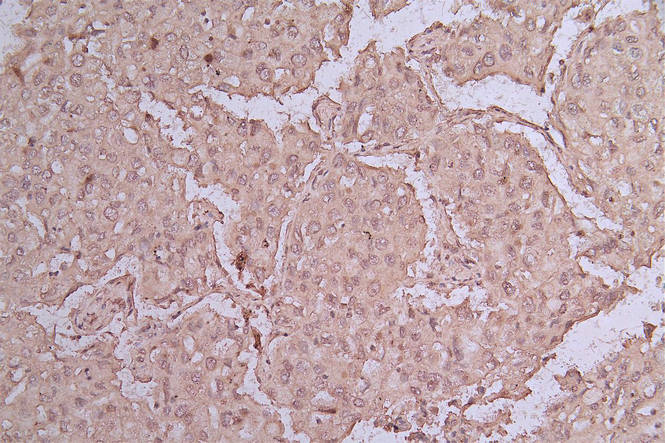

IHC image of CSB-RA159341MA1HU diluted at 1:50 and staining in paraffin-embedded human lung cancer performed on a Leica BondTM system. After dewaxing and hydration, antigen retrieval was mediated by high pressure in a citrate buffer (pH 6.0). Section was blocked with 10% normal goat serum 30min at RT. Then primary antibody (1% BSA) was incubated at 4°C overnight. The primary is detected by a Goat anti-rabbit polymer IgG labeled by HRP and visualized using 0.05% DAB.

CSB-RA159341MA1HU

IHC image of CSB-RA159341MA1HU diluted at 1:50 and staining in paraffin-embedded human pancreatic tissue performed on a Leica BondTM system. After dewaxing and hydration, antigen retrieval was mediated by high pressure in a citrate buffer (pH 6.0). Section was blocked with 10% normal goat serum 30min at RT. Then primary antibody (1% BSA) was incubated at 4°C overnight. The primary is detected by a Goat anti-rabbit polymer IgG labeled by HRP and visualized using 0.05% DAB.